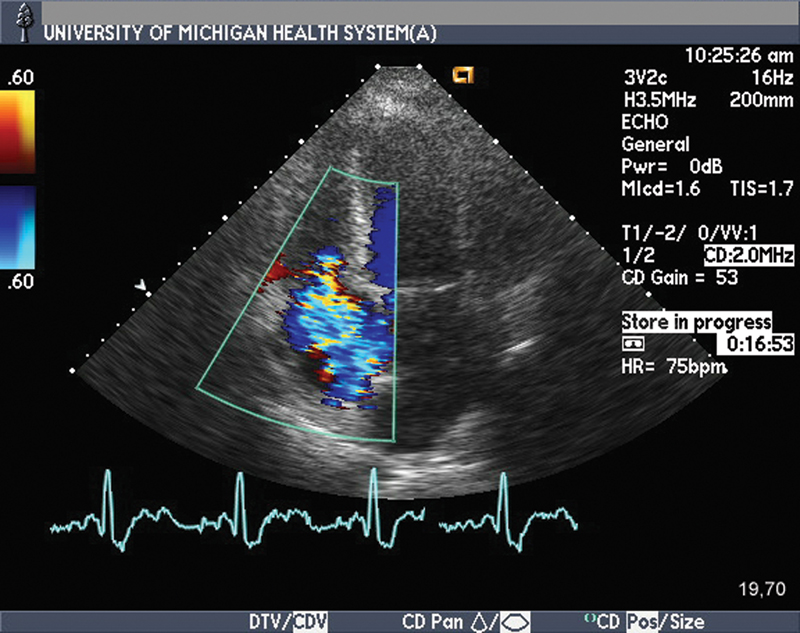

فحوصات تشخيصية لبعض امراض القلب والشرايين التاجية